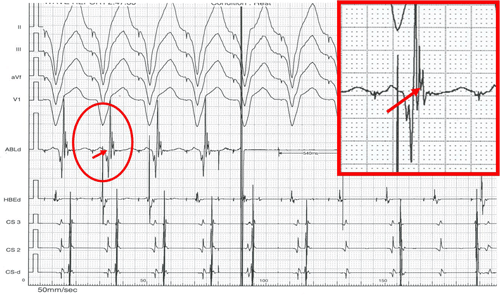

Hình 8: Triệt đốt đường dẫn truyền phụ điển hình trong lúc nhịp xoang. Kết quả xuất hiện ngay sau 372 ms (hết hình ảnh WPW), điện đồ vị trí đích (trong ô vuông đỏ) có sóng nhĩ đi trước và trộn lẫn với sóng thất.

Hình 9: Triệt đốt đường dẫn truyền phụ điển hình trong lúc tạo nhịp thất phải. Kết quả xuất hiện ngay sau 540 ms (xuất hiện hình ảnh phân ly thất-nhĩ), điện đồ vị trí đích (trong ô vuông đỏ) có sóng thất đi trước và sóng nhĩ đi ngay sát sau sóng thất.